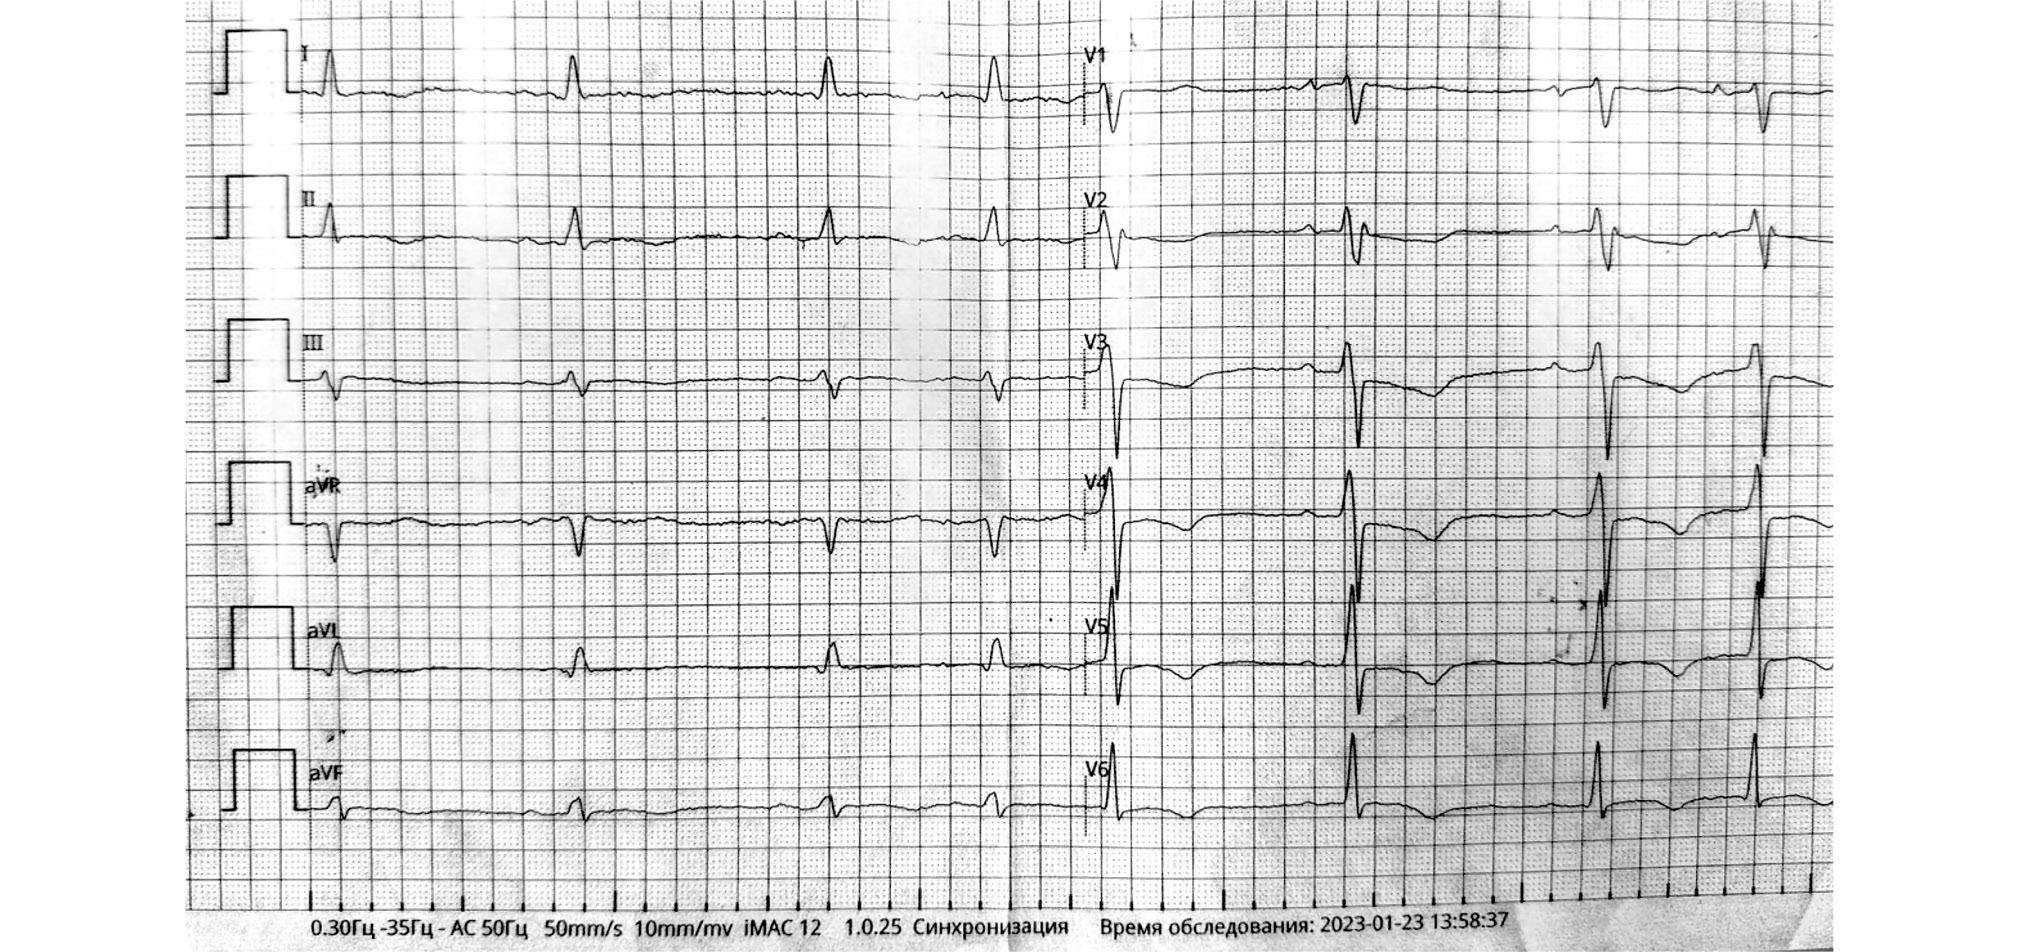

Результаты проведённых в ЦРБ лабораторных исследований представлены в табл. 2 и 3. Для удобства сравнения и анализа динамики в указанные таблицы внесены также более поздние анализы, выполненные в ОККД. За время наблюдения состояние пациентки сохранялось без улучшения. Повторные рентгенологические исследования 23 и 30 января (см. табл. 1) не показали выраженной положительной динамики. Анализы мокроты на микобактерии туберкулёза были трижды отрицательные. При нахождении в стационаре у пациентки регистрировался синусовый ритм, инверсия зубца Т в грудных отведениях (рис. 2), затем 31.01.2023 зарегистрирована полная АВ-блокада с ЧСС 40 уд./мин (рис. 3), в связи с чем пациентка транспортирована по санавиации в ОККД.

Рис. 2. Электрокардиограмма пациентки Б. от 23.01.2023 при стационарном лечении в Центральной районной больнице.

Fig. 2. Electrocardiogram of patient B. dated January 23, 2023 during inpatient treatment at the Central District Hospital.

Рис. 3. Электрокардиограмма пациентки Б. от 31.01.2023 перед переводом в Областной клинический кардиологический диспансер.

Fig. 3. Electrocardiogram of patient B. dated January 31, 2023 before transfer to the Regional Clinical Cardiodispanser.